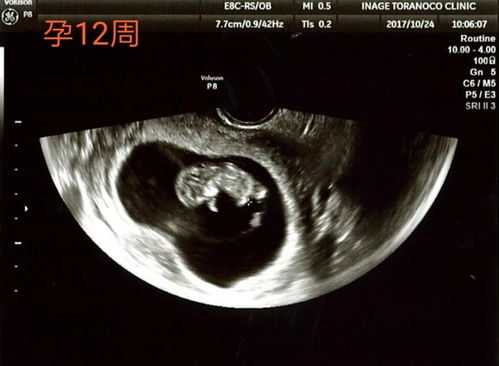

20周胎儿系统B超检查,又称为大排畸检查,是孕期中的一项重要检查。这一阶段的胎儿已经发育到一定程度,器官结构基本形成,通过B超检查可以全面了解胎儿的生长发育情况,及时发现并排除严重的胎儿畸形。

一般来说,20周胎儿系统B超检查的最佳时间为妊娠20-24周。此时,胎儿各器官已经发育成熟,羊水量适中,胎儿相对容易变换体位,有利于超声筛查胎儿结构。